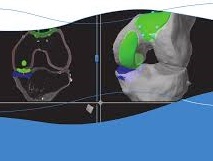

Είναι μέρος της άρθρωσης του γόνατος στην πρόσθια επιφάνειά του. Αποτελεί την άρθρωση μεταξύ επιγονατίδας και μηρού. Συγκεκριμένα, η οπίσθια επιφάνεια της επιγονατίδας, με μορφή «καρίνας», αρθρώνεται με την πρόσθια επιφάνεια του μηρού σε μια υποδοχή που ονομάζεται τροχιλία. (εικόνα 1 ). Η επιγονατίδα λειτουργεί σαν «υπομόχλιο» κατά την κάμψη – έκταση του γόνατος, ενισχύοντας τη δράση του εκτατικού μηχανισμού. Πρακτικά δηλαδή ενισχύει την έκταση (το «τέντωμα») του γόνατος υπό τη δράση του τετρακεφάλου μυός. (εικόνα 2 ). Η άρθρωση δέχεται πολύ ισχυρά συμπιεστικά φορτία. Είναι ενδεικτικό ότι ο χόνδρος που καλύπτει την οπίσθια επιφάνεια της επιγονατίδας είναι ο παχύτερος σε όλο το ανθρώπινο σώμα, ακριβώς για να μπορέσει να ανταποκριθεί σε αυτά τα φορτία.

Η οπίσθια επιφάνεια της επιγονατίδας και η πρόσθια του μηρού αντικαθίστανται ανάλογα του μεγέθους και της ανατομίας του γόνατός σας με το κατάλληλο εμφύτευμα. (εικόνα 9 ) Ειδικά όσον αφορά τις οστεοτομίες στην πρόσθια επιφάνεια του μηρού, η τεχνική και οι χρησιμοποιούμενοι οδηγοί έχουν επίσης εξελιχθεί σοβαρά. (εικόνα 10 εικόνα 11 και εικόνα 12)